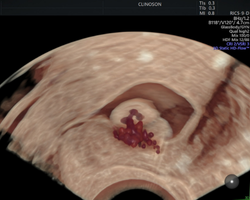

Hoje, atuo ajudando mulheres a terem diagnósticos precisos e tratamentos modernos, incluindo o cuidado e diagnóstico de miomas uterinos, fertilidade e acompanhamento na medicina fetal.

Também, especializei-me em métodos como a ultrassonografia avançada para endometriose e o HyCoSy — um exame moderno e menos invasivo que traz conforto, precisão e segurança para mulheres que enfrentam dificuldades como infertilidade e dores pélvicas.

- Pioneiro na realização de HyCoSy – Histerossonossalpingografia com contraste de microbolhas em Porto Alegre

Investigando a infertilidade? Conheça o HyCoSy

Antes de mais nada, a investigação da infertilidade é uma etapa fundamental para casais que sonham em ter filhos e